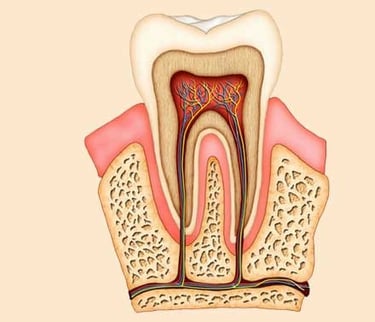

A root canal treatment is a dental procedure to remove inflamed or infected pulp on the inside of the tooth which is then carefully cleaned and disinfected, then filled and sealed. Root canal treatment is designed to eliminate bacteria from the infected root canal, prevent reinfection of the tooth and save the natural tooth.

First, the dentist removes everything that is inside the root canal. With the patient under local anesthesia, the dentist makes a small access hole on the surface of the tooth and removes the diseased and dead pulp tissue with very small files.

2. Filling the root canal

After root canal therapy, the tooth is dead. The patient will no longer feel any pain in that tooth because the nerve tissue has been removed, and the infection has been eliminated.

3. Adding Filling or a Crown

However, the tooth will be now more fragile than it was before. A tooth with no pulp must receive its nourishment from the ligament that attaches the tooth to the bone. This supply is adequate, but in time, the tooth will become more brittle, so a crown or filling offers protection..

Root canal therapy will usually save the tooth and eliminate the pain.

If the tooth cannot be saved, the next best option is an implant.

However, saving the natural tooth is best, if possible, because nothing functions as well as a natural tooth.